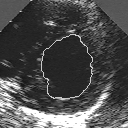

DETECTION AND TRACKING OF ANATOMICAL STRUCTURES USING DEFORMABLE TEMPLATES AND A NOISE MODEL ESTIMATION IN AN ECHOGRAPHIC SEQUENCE

In this work, we present a new method to shape-based segmentation of deformable anatomical structures in medical images and validate this approach by detecting and tracking the endocardial border in an echographic image sequence. To this end, a global prior knowledge of the endocardial contour is captured by a prototype template with a set of admissible deformations to take into account its inherent natural variability over time. In this approach, the data likelihood model rely on an accurate statistical modeling of the grey level distribution of each class present in the image. The parameters of this distribution mixture are given by a preliminary estimation step which takes into account the distribution shape of each class. Then the tracking problem is stated in a Bayesian framework where it ends up as an optimization problem. This one is then efficiently solved by a genetic algorithm combined with a steepest ascent procedure. This technique has been successfully applied on synthetic images and on a real echocardiographic image sequence. This method seems to be particularly well suited to handle ultrasound images with strong speckle noise on which edge information cannot be exploited. Finally, the local and global minimization procedure we propose is fast, robust and do not require initialization of the template close to the desired solution. Initialization may be defined at random, leading to segmentation and tracking procedure that are completely data driven. (slides)

Figure 1:   Tracking of the endocardial contour in a medical echographic sequence at different time frames during the cardiac cycle. From top left to bottom right : frame 1, 4, 6, 9, 12, 13, 18, 20, 27, 30, 35, 40, 41, 44, 46.